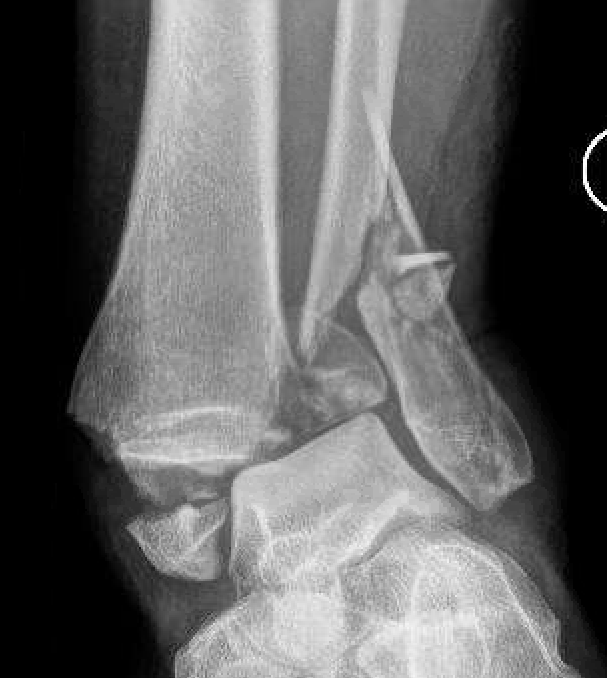

Lateral talar shift / increased medial clear space / deltoid ligament injury

Ankle Fracture Increased Medial Clear SpaceAnkle Fracture Increased Medial Clear Space 2Maisonnerve

Tibia / fibular overlap < 1mm / syndesmotic injury

Ankle Fracture Syndesmosis WidenedAnkle Diastasis

Ankle dislocation

Reduction under conscious sedation

- protects skin medially

- conscious sedation in emergency department

- well moulded cast

- unstable ankles need monitoring for loss of reduction

- can need external fixation to maintain position

Dislocationdislocationdislocation